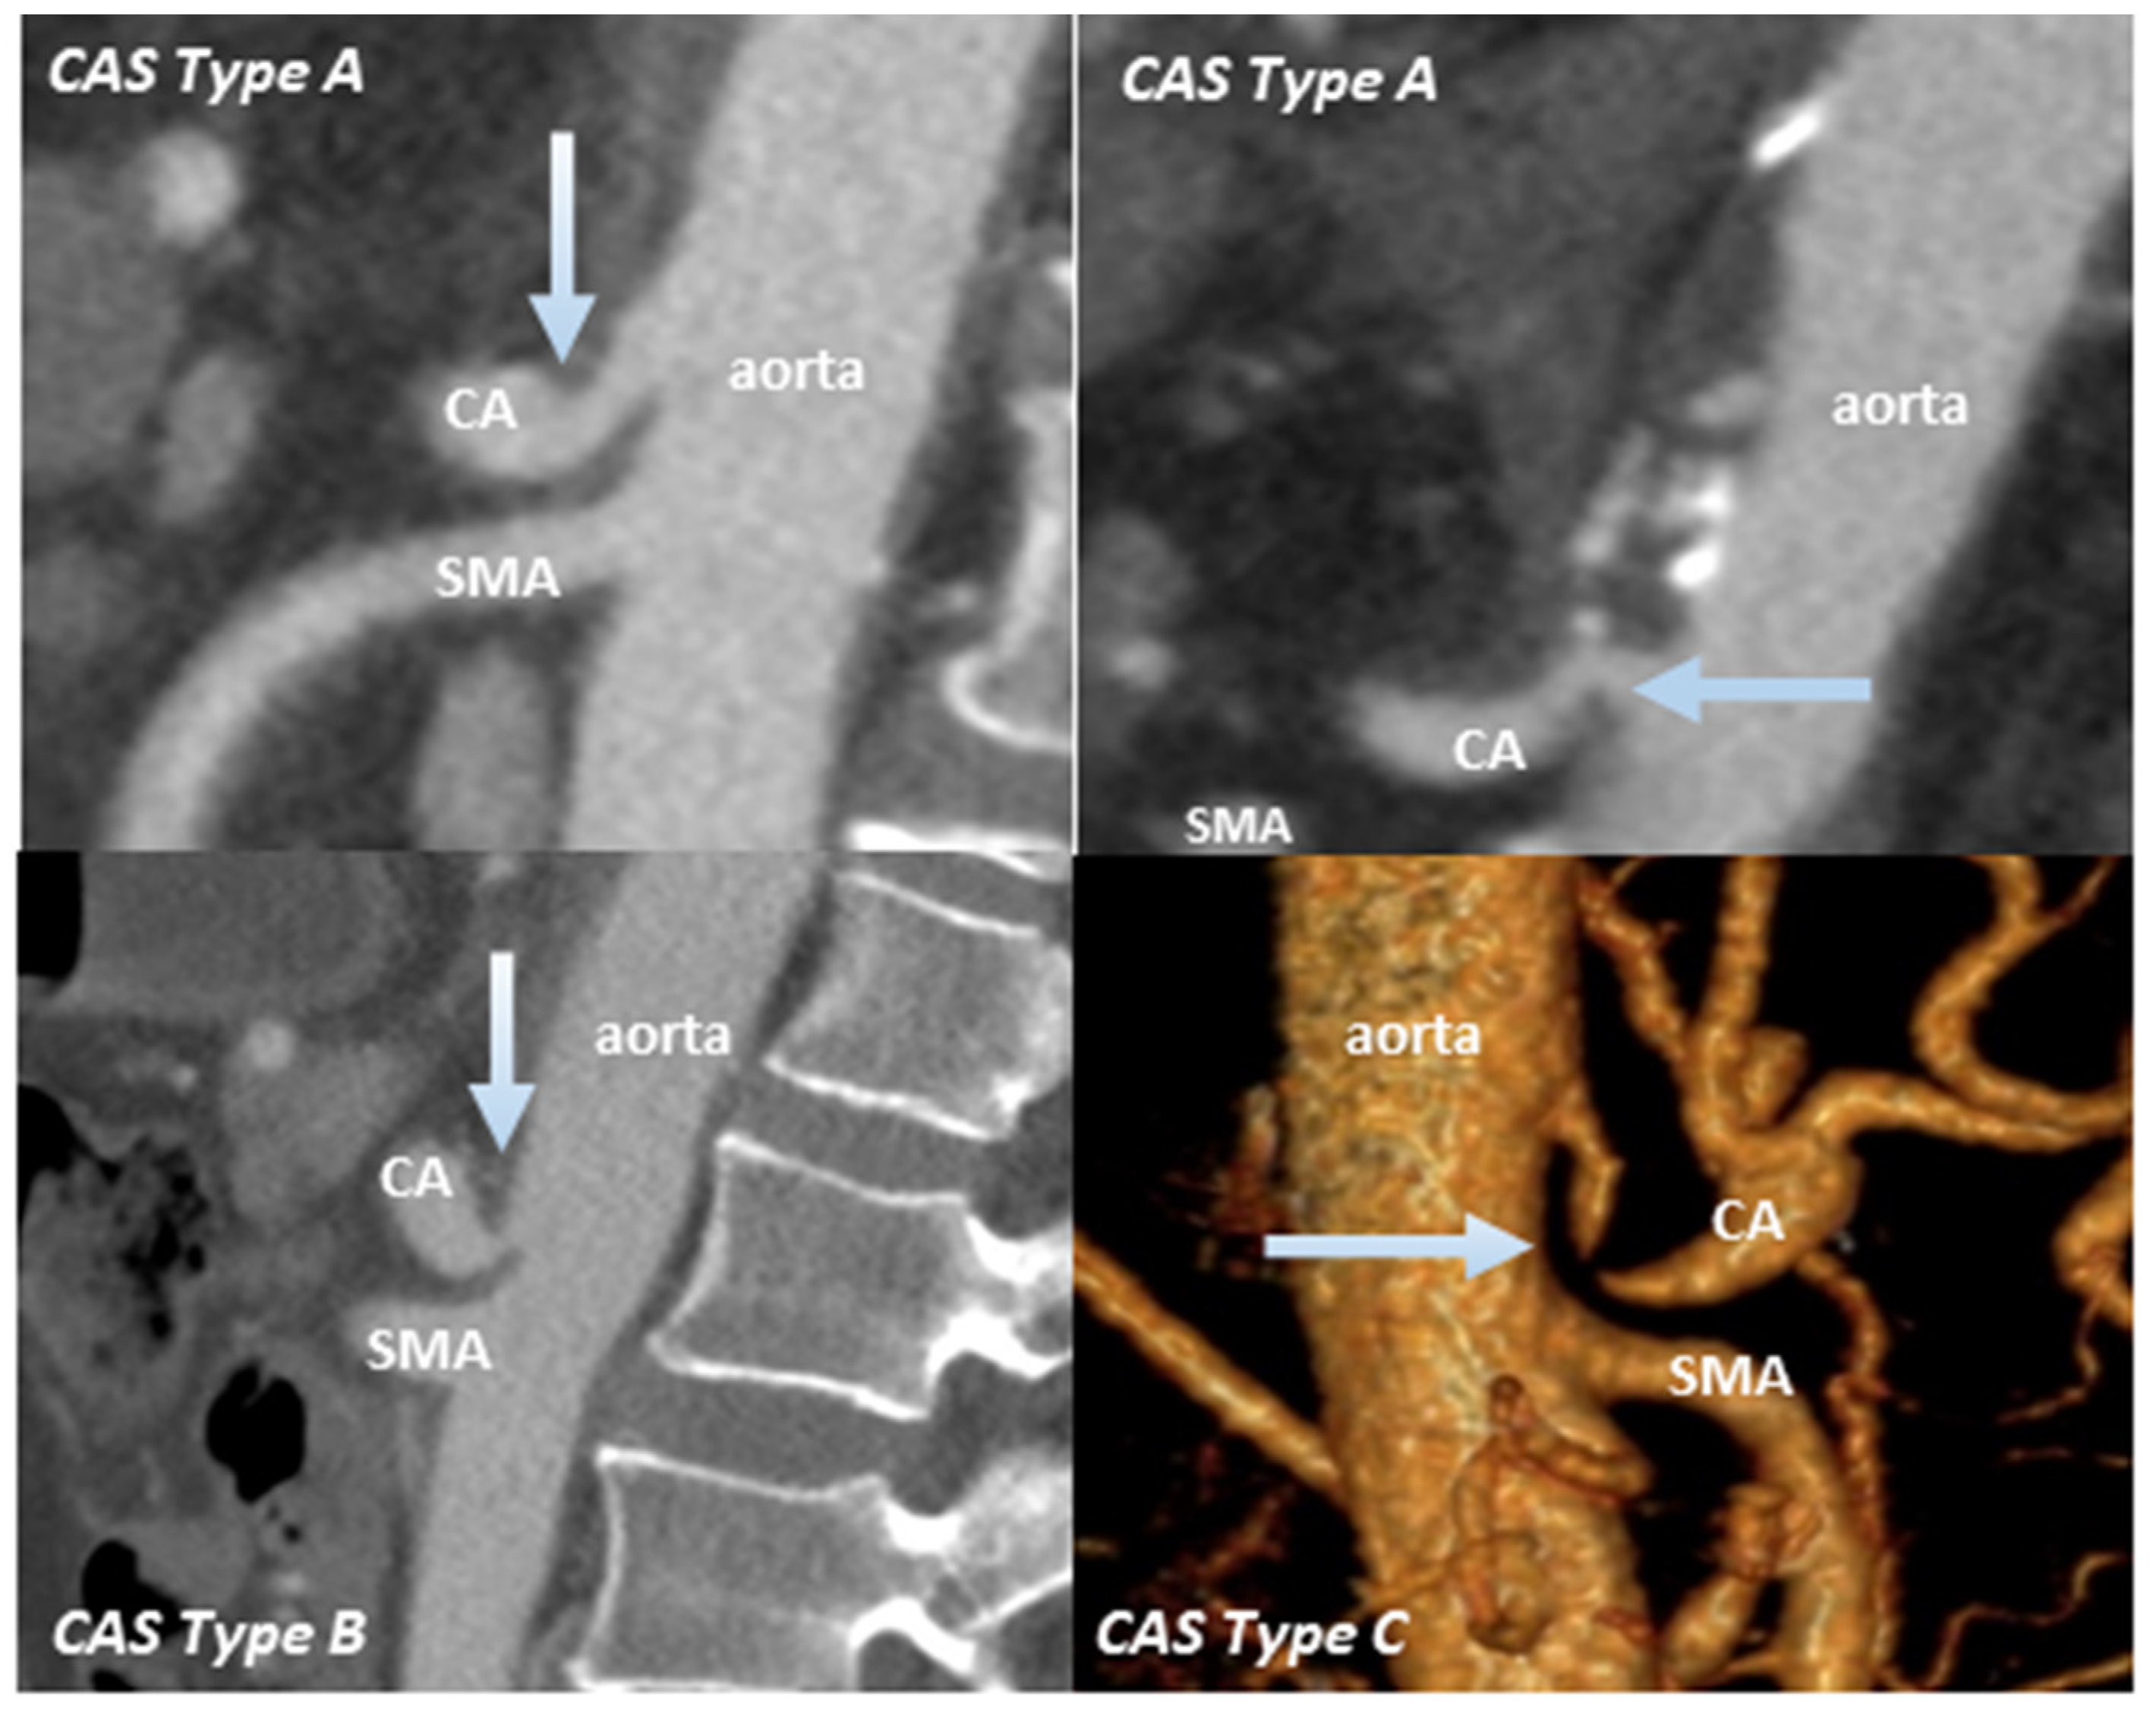

- Sugae, T.; Fujii, T.; Kodera, Y.; Kanzaki, A.; Yamamura, K.; Yamada, S.; Sugimoto, H.; Nomoto, S.; Takeda, S.; Nakao, A. Classification of the celiac axis stenosis owing to median arcuate ligament compression, based on severity of the stenosis with subsequent proposals for management during pancreatoduodenectomy. Surgery 2012, 151, 543–549. [Google Scholar] [CrossRef]

| CAS by MAL Compression | Type A | Type B | Type C |

|---|---|---|---|

| Stenosis rate, % | ≤50 | 50–80 | ≥80 |

| Stenosis length, mm | ≤3 | 3–8 | ≥8 |

| Distance from aorta, mm | ≥5 | ≥5 | small |